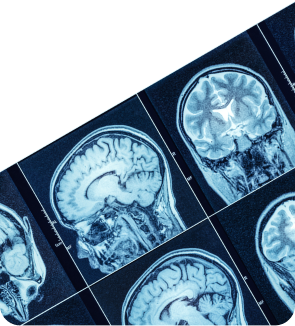

МРТ: точная диагностика на современном оборудовании

Магнитно-резонансная томография головы в Клинике Эксперт в Красноярске – современный и самый точный метод обследования этой части тела, позволяющий поставить диагноз в кратчайшие сроки. Статистика проведения всех МРТ исследований говорит, что более половины из них приходится на голову.

Аппараты с напряжённостью магнитного поля 1,5 Тесла — это высокопольные томографы. Они выполняют изображения со срезом толщиной от 1 мм, что позволяет заметить даже малейшие отклонения от нормы.